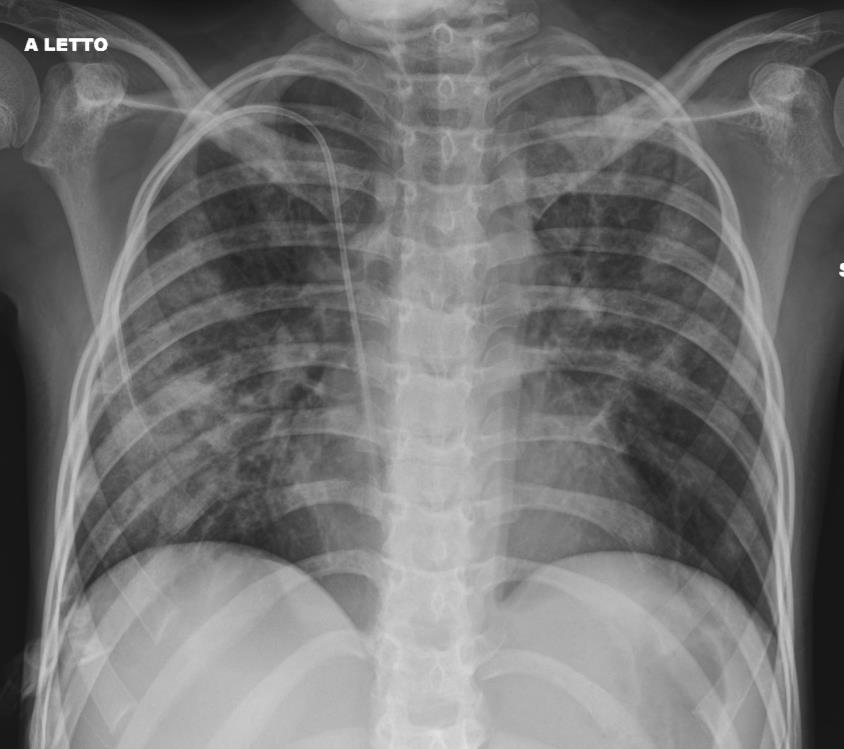

Pediatric COVID-19: MIS-C

Thoracic abnormalities

Cardiovascular abnormalities

Cardiomegaly

CHF or cardiogenic edema

Pulmonary parenchymal abnormalities

Lower lobe atelectasis

Bilateral opacities( ARDS)

Consolidation

Pleural abnormalities

Small pleural effusion

Mediastinal and hilar lymphadenopathy

MIS-C: Heart failure